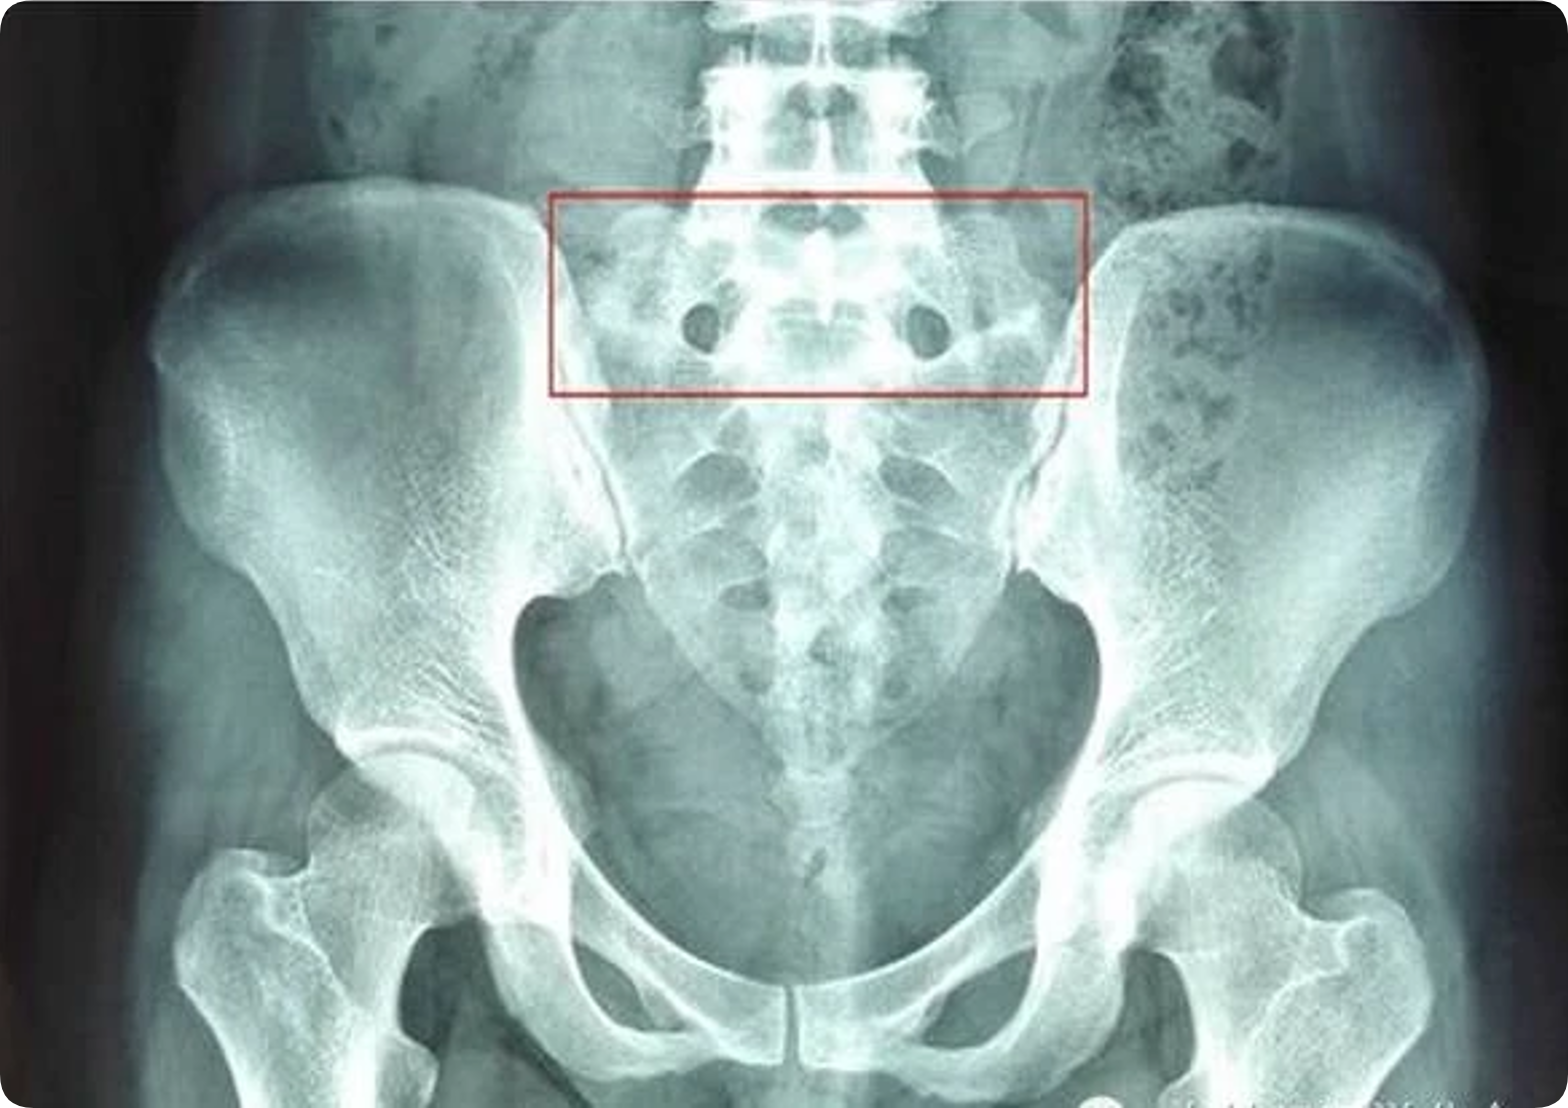

第五腰椎横突肥大(L5腰椎横突肥大)是指第五腰椎横突发育异常, 一般临床无症状,但随着年龄的增长、劳损或外伤等,均可出现腰腿痛, 也是导致患者发生慢性腰腿痛的原因之一

对L5腰椎横突肥大引起下腰痛的原因进行分析认为,L5腰椎横突粗 壮且轻度上翘,与髂骨基本平行,但有一定间隙。L4、5脊神经联合支下 行经过L5横突前方,当L5横突出现肥大,可直接向下压迫L5神经,对 其可产生压迫,加之患者腰部活动,可引起坐骨神经压迫症状;L5 腰椎 横突处为肌肉、韧带附着点,最易引发损伤,而横突越大,越易引发附着 点损伤,引起局部无菌性炎症,产生胺类、缓激肽及乳酸等代谢产物,并 在局部蓄积引起腰痛。这些代谢物可使其附近毛细血管扩张,通透性加强, 局部组织充血、水肿,引起纤维蛋白渗出增加,出现粘连,如无进一步治 疗,可引起横突更为肥大,导致患者症状再次加重;L5 腰椎横突肥大与 骶髂骨接触或假关节形成,腰椎呈骶化趋势或骶化不全,可能使这种机会 增加,当肥大横突与骶骼骨接触时,由于二者间间隙较小或无间隙,活动 或暴力损伤均可能引起周围软组织及骨膜发生损伤,引起下腰部痛。另外, L5 腰椎横突肥大与骶股长骨形成假关节时,由于关节软骨较薄或缺如, 关节面高低不平,间隙狭窄,形成损伤性关节炎;随着时间的延长,年龄 的增长,关节面增生硬化,出现骨唇,软组织充血水肿,使挤压的神经末 梢产生疼痛,甚至可引起相信椎间孔变窄,刺激L5 神经根,引起下肢放 射性疼痛,或麻木。

总之,L5 腰椎横突肥大,多发于青壮年、体力劳动者,由于肥大的 横突或形成的假关节压迫L5 神经、损伤附着点等原因,,是导致患者慢 性腰腿痛的原因之一,在诊断上可结合患者的临床症状及X 线片等检查 进行确诊,并对症给予治疗,解除患者痛苦。